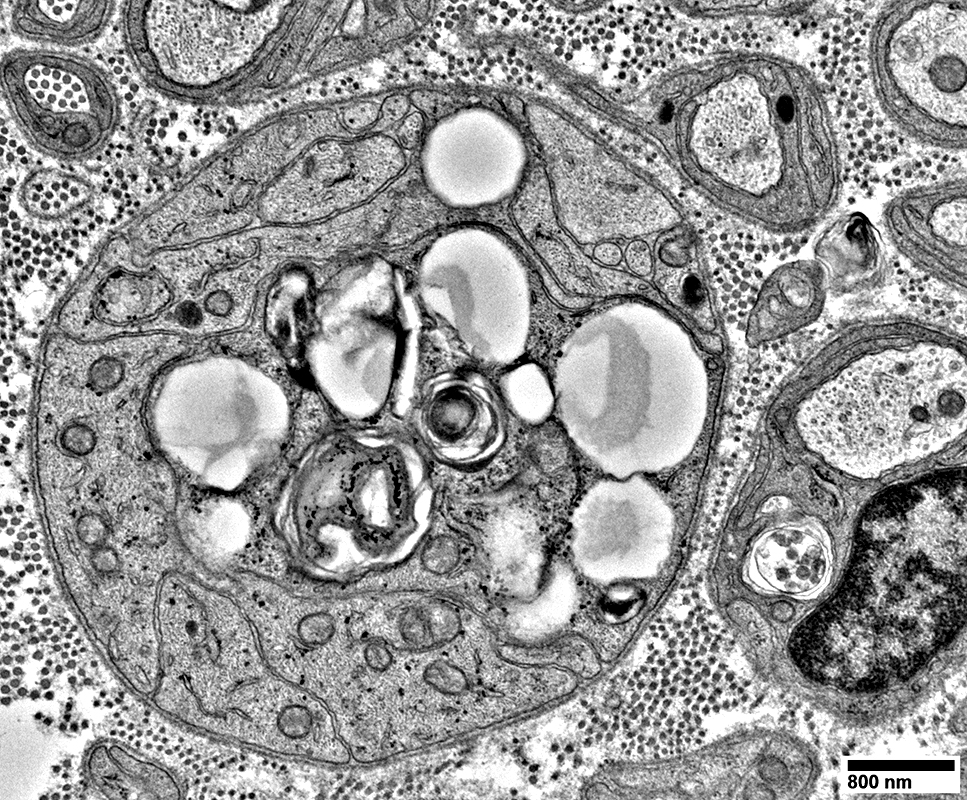

Schwann Cells

Some contain Lipid debris

Myelin Damage: Lipid Droplets & Ovoids in Schwann cells

Myelin Damage: Lipid Droplets & Myelin debris in Schwann cells

Myelin Damage: Lipid Droplets & some Myelin debris in Schwann cells